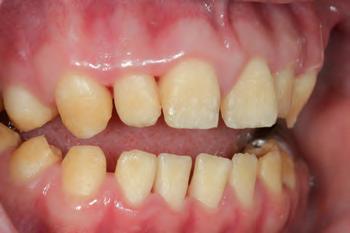

The patient was an 18-year-old male with a confirmed family history of Xlinked AI, who was otherwise in good health and non-smoking. Upon initial clinical presentation, a low-caries-risk, complete adult dentition from second molar to second molar was present, which was globally affected by pitted, hypoplastic and hypomineralised AI, dento-alveolar disproportion and an unusual generalised open occlusion, characterised by one occlusal contact at the right first molar region in the maximum intercuspation position (MIP). Historical paediatric management of the dentition involved placement of stainless steel crowns at the first permanent molar sites to protect the emerging dentition from post-eruptive breakdown and loss of occlusovertical dimension during the mixed dentition phase.6 On adult presentation, all but the UR6 stainless steel crown remained intact. Oral hygiene was poor, with evidence of plaque-induced chronic gingivitis (Figure 1). The patient reported experiencing severe, widespread hypersensitivity upon hot, cold, osmotic and masticatory stimuli, and feeling aesthetically self-conscious. The patient was seeking comprehensive fixed prosthodontic care and was well informed about the nature of such treatment, having witnessed his elder siblings undergo similar treatment.

1: The patient’s initial situation on clinical presentation to the tertiary care referral centre. The dentition is globally af fected by amelogenesis imperfecta, associated with dentoalveolar disproportion and an unusual presentation of open occlusion.